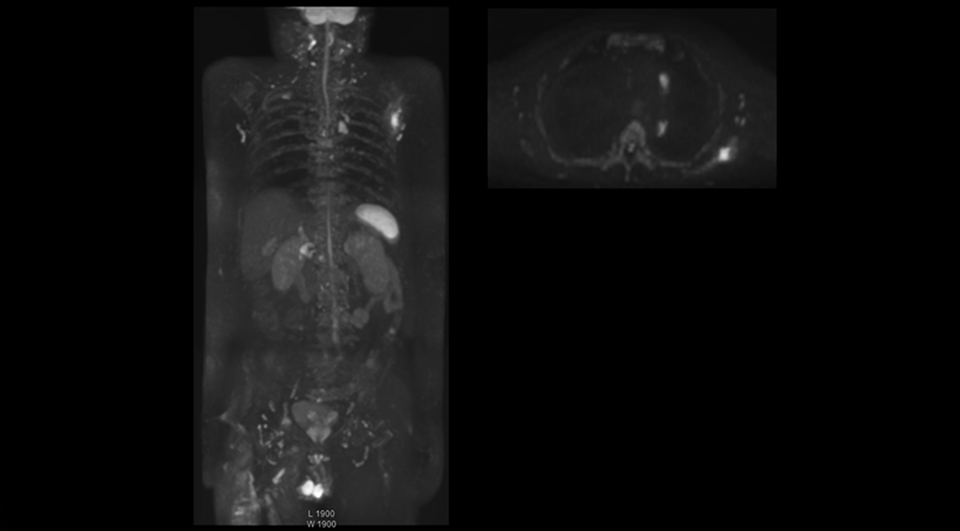

Radiologist Hiroshi Nobusawa, MD, PhD, explains that the coronal DWIBS protocol for whole body DWI is excellent for visualizing lesions in oncology patients. “About 90% of the DWIBS exams are done in this type of patients. The remainder of DWIBS exams are performed to gain information in cases of fevers of unknown origin,” he says. in image acquisition and postprocessing algorithms.”“mDIXON TSE sequences allow simultaneous characterization of morphological changes from the in-phase T2-weighted images and visualization of edematous changes, thanks to the water T2-weighted images from the same acquisition. Anatomical and morphological considerations could be a partial or complete ligament tear, a bony avulsion or hematoma.” “For soft tissue assessment mDIXON brings similar benefits. For example in one T2-weighted mDIXON TSE acquisition, having the multiple contrasts helps us assess abnormalities in peripheral nerves fascicles, which may be due to anatomical or inflammatory changes..” “In peripheral joints, we get good image quality in difficult areas with mDIXON TSE. Fat suppressed images appear homogeneous over the entire image, even with large coverage at 3.0T – for instance in scapular or hip girdles – or in the bearing areas or around metal prostheses*, where fat suppression is often deficient with STIR or spectral fat suppression, causing diagnostic difficulties. If a diagnostic image is right the first time, we don’t need to repeat or add a sequence.” “mDIXON TSE sequences allow simultaneous characterization of morphological changes from the in-phase T2-weighted images and visualization of edematous changes, thanks to the water T2-weighted images from the same acquisition. Anatomical and morphological considerations could be a partial or complete ligament tear, a bony avulsion or hematoma.” “For soft tissue assessment mDIXON brings similar benefits. For example in one T2-weighted mDIXON TSE acquisition, having the multiple contrasts helps us assess abnormalities in peripheral nerves fascicles, which may be due to anatomical or inflammatory changes..”

“The DWIBS sequence’s value in oncology cases is due to the high contrast it creates between lesions and surrounding tissue. Whole body DWI is requested by physicians who need to clarify TNM staging or determine therapeutic strategies, oncologists in need of diagnosis or follow-up scans, surgeons who need to see the presence of distant lesions that are sometimes difficult to detect by CT before surgery, and urologists for the evaluation of bone lesions, and the effect of chemotherapy and radiotherapy.”

“Switching to coronal DWIBS – rather than axial – further shortens scan time,” says Mr. Naka. “Important is that a dS SENSE factor of 5 shortens exam time while high image quality can be maintained, thanks to Ingenia’s dStream architecture.” He adds that the coronal orientation also avoids artifacts that are specific to combining axial images.

“When we use a coronal DWIBS acquisition, we can perform a full whole body examination, including other required sequences, within 30 minutes,” he says.